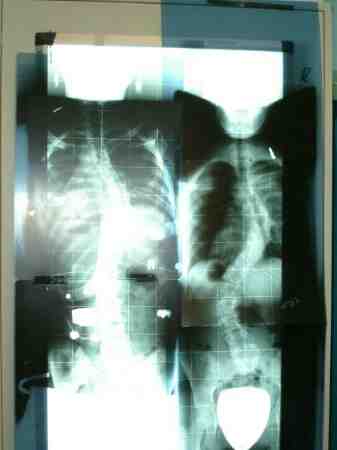

Ein Bild was alles sagt

Jennifer vorher und mit Korsett

Jennifer1.jpg (13.16 KiB) 14492 mal betrachtet

Jennifer vorher unten (ich kann den Namen nicht behalten Lum...)

62Grad vorher

Im Korsi 18 Grad

Oben

32 Grad vorher

I.K. 17 Grad

Ansonsten sieht Jennis RöBi im Korsett ja fast identisch aus mit meinem damals. Sieht sogar ein bischen gerader aus, finde ich. Bin mal gespannt auf die genauen Daten!